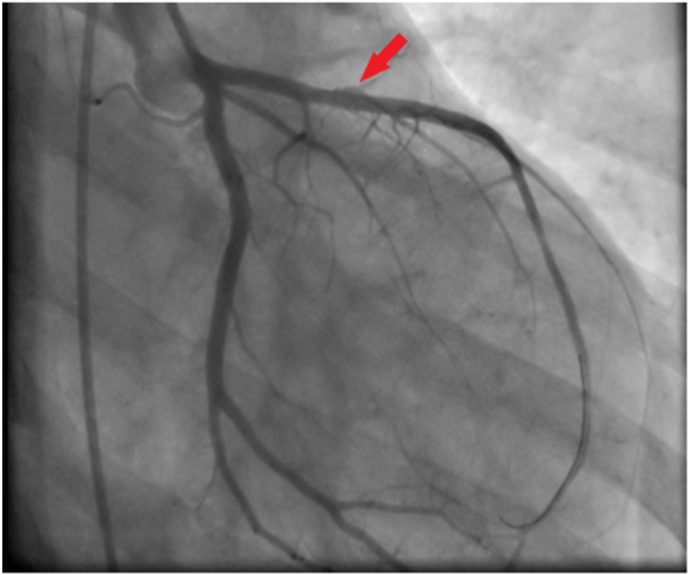

Coronary angiography was performed and a significant stenosis in the middle segment of the left anterior descending artery (LAD) was noted (Fig. 3). A Percutaneous Coronary Intervention (PCI) of the LAD was realized with the implantation of a new generation-stent (Fig. 4).